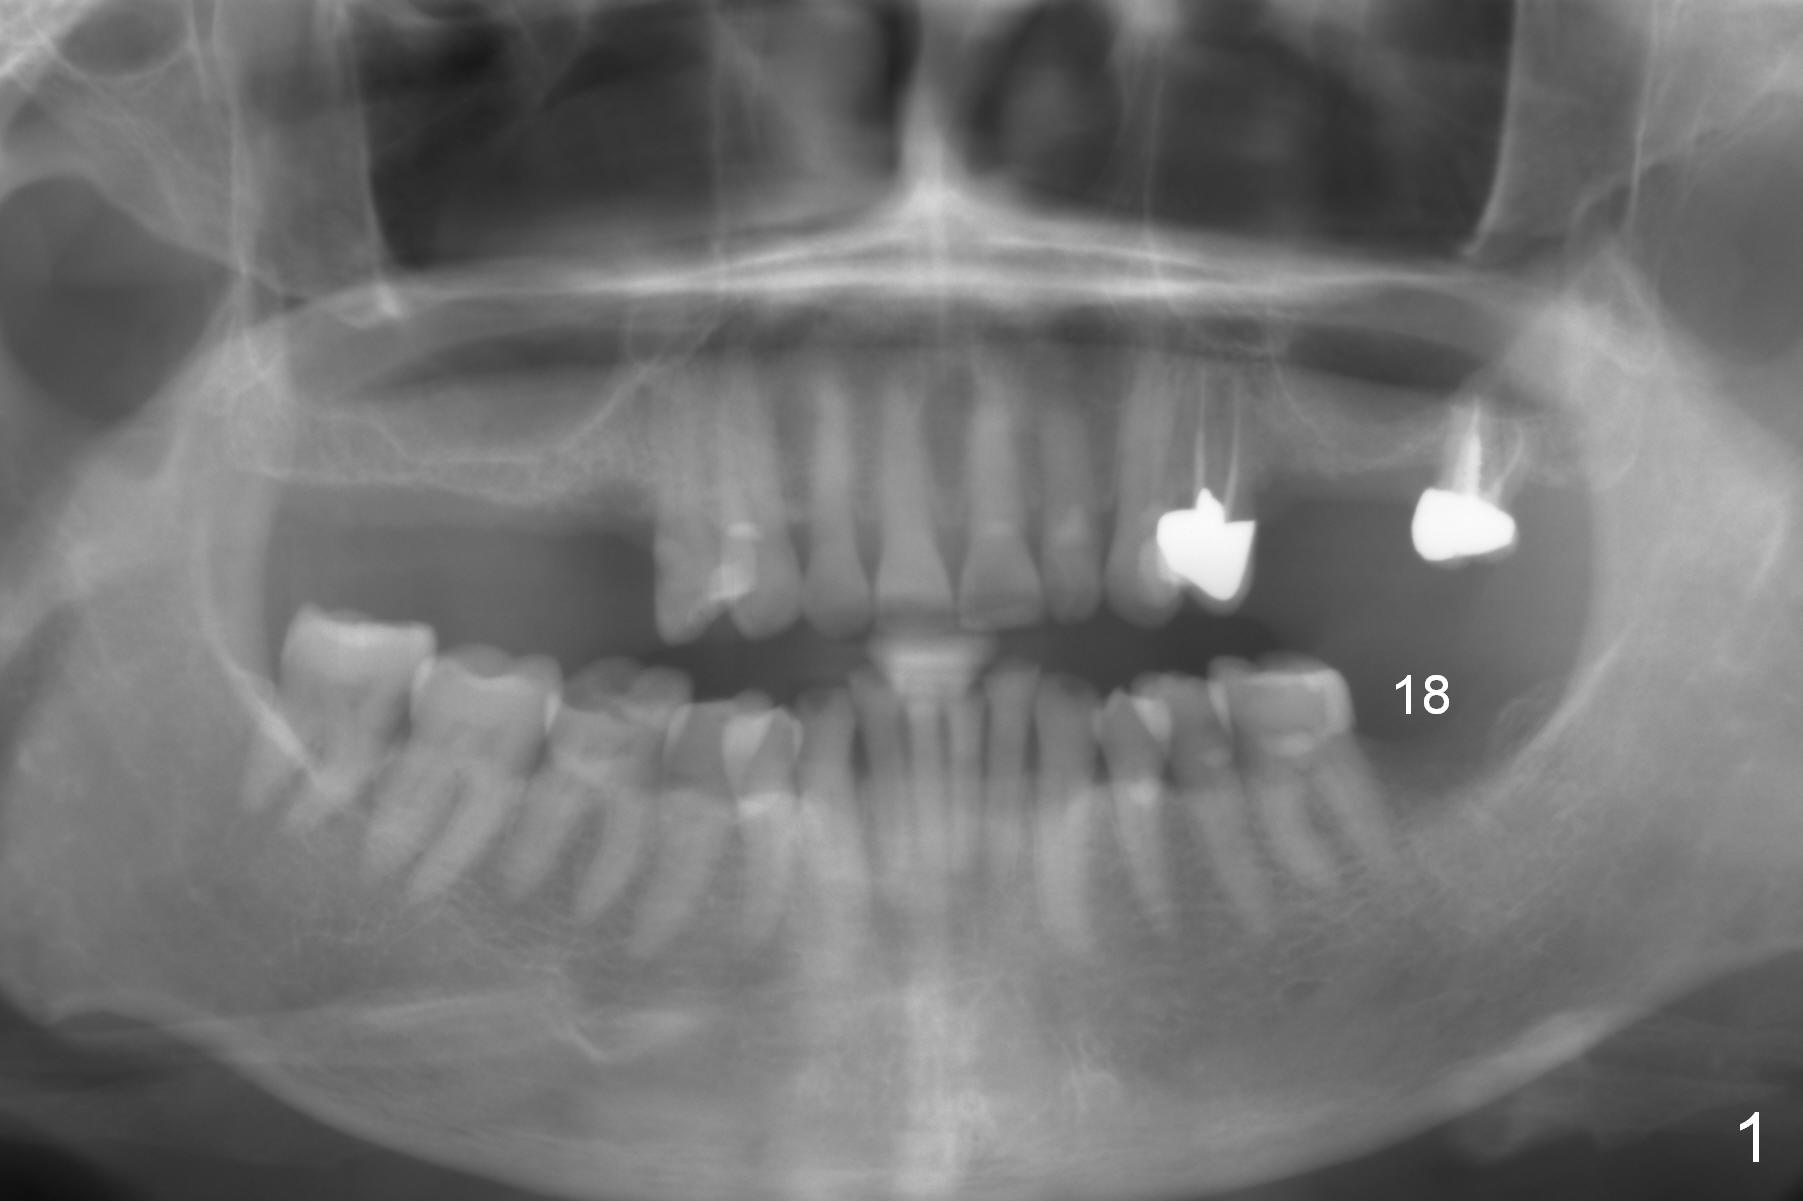

A 65-year-old woman is afraid of dentistry. After loss of the tooth #18 (Fig.1 with upper RPD), she feels necessary to have an implant (Fig.2). Since the ridge is wide (Fig.3), a flapless approach is adopted (Magic Split, measure the diameter of its handle). After 1.6 mm pilot drill (9 mm stopper) and Marking Drill (know the diameter of the large portion), use 4.8 mm Magic Drill (spacer set 2.5 mm, stopper 11 mm). Try in 5.5x9 mm dummy implant and most likely 6x9 mm definitive one.